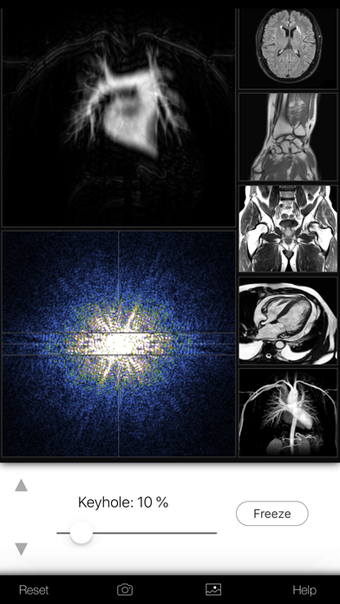

Een volledige versie app voor iPhone, door Eltjo Haselhoff.

A K-Space Odysseyis een app met volledige versie voor iPhone, die deel uitmaakt van de categorie ' Geneeskunde'.

Over A K-Space Odyssey voor iPhone

Een K-Space Odyssey is beschikbaar voor iOS 12.1.2 of hoger. De huidige versie van de software is 1.9.1 en u kunt deze alleen in het Engels krijgen.